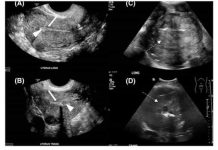

Sve više žena umire od raka maternice: 6 jasnih znakova da se ovaj opasni tumor razvija u tijelu!

Rak maternice može se podijeliti u dvije različite vrste – češći rak endometrija (rak endometrija)...